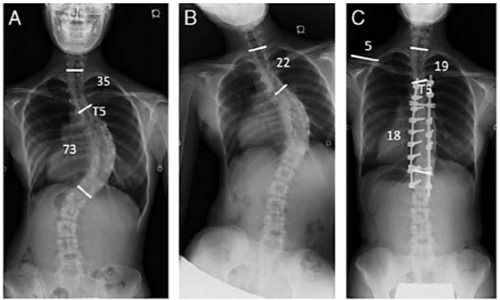

На четвертой стадии, когда угол отклонения превышает 40 градусов, необходима операция.

Операция проходит в несколько этапов. Сначала необходимо выпрямить позвоночник, затем его фиксируют с помощью специального металлического импланта.

Операция по исправлению позвоночника осуществляется в два этапа — выравнивание и фиксация.

Такой имплант устанавливается на всю жизнь, он не отторгается организмом и не требует замены. Уже через два дня после операции пациент может передвигаться самостоятельно, а на пятый день его готовят к выписке, учитывая его состояние.